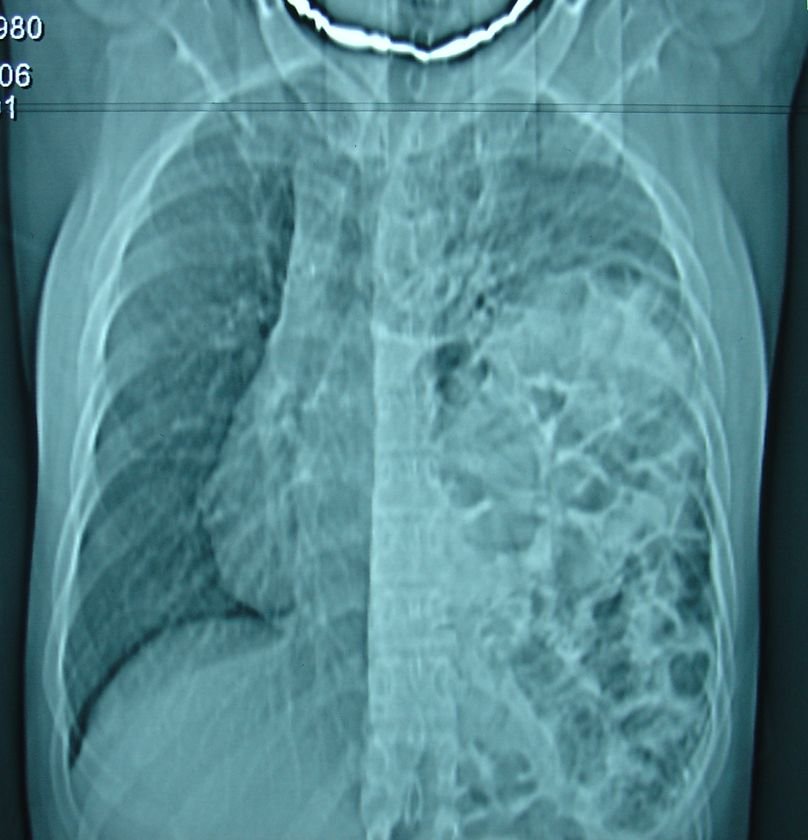

Şəkil 3. Diafraqma yırtığı